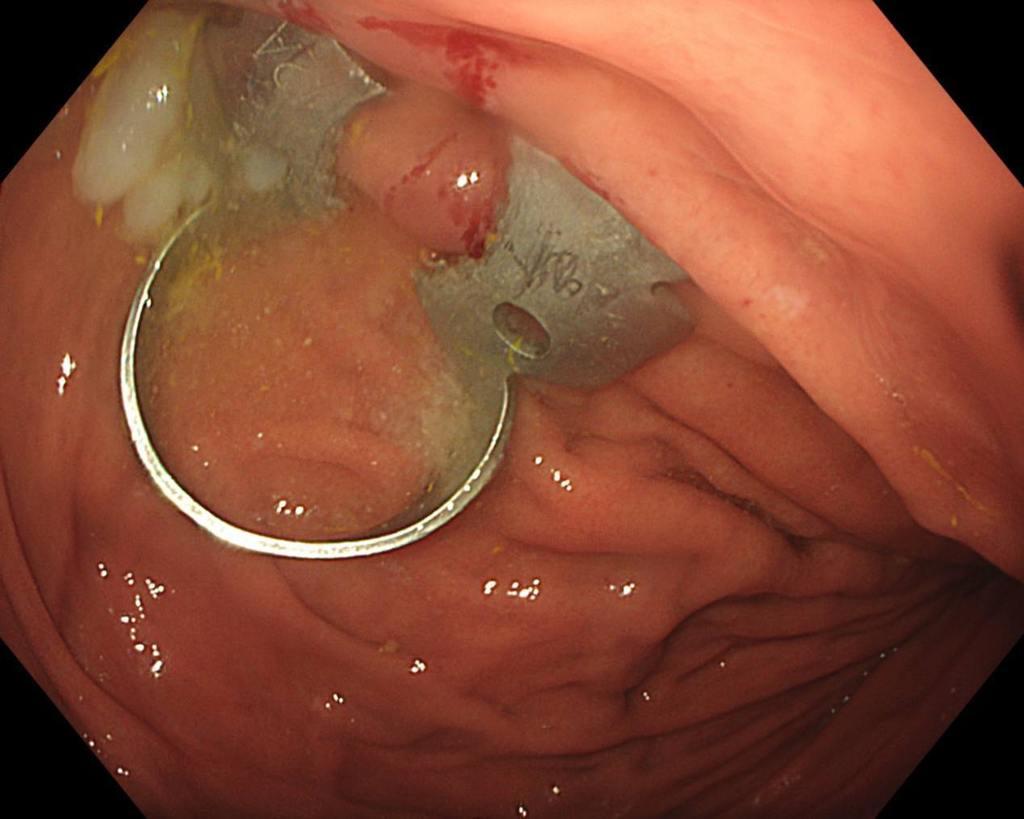

— Для извлечения инородного тела мы выполнили гастроскопию, в ходе которой захватили стоматологическую скобу эндоскопической петлей. Так как инородный предмет был острый, то это создавало высокие риски травмировать слизистую, мы поэтапно провели скобу через пищевод, устье пищевода и гортаноглотку. Процедура длилась около 10 минут и прошла успешно. При контрольном осмотре травматических дефектов слизистой не определялось, — сказала врач-эндоскопист Анастасия Лазарева.